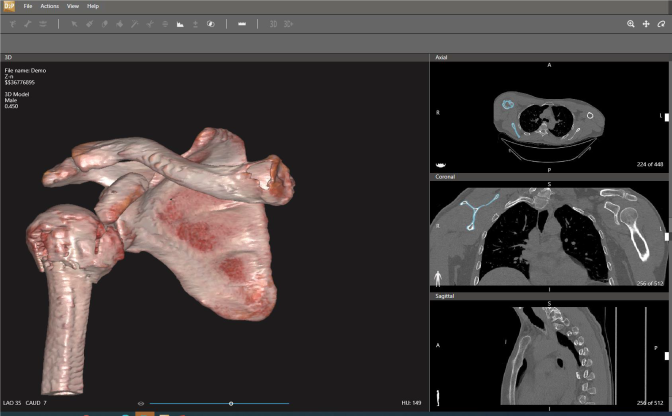

Diseño e Impresión 3D: Desarrollar soluciones impresas para los proyectos que necesiten algún tipo de prototipo o modelo funcional ya sea mecánico, anatómico o de estudio, que sean parte esencial de los proyectos de investigación. Contamos con la herramienta D2P "Dicom to Print" que permite crear modelos digitales 3D con calidad de diagnóstico e impresiones físicas 3D de forma rápida y fácil